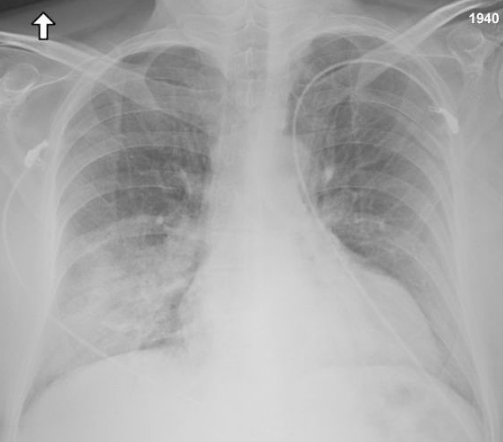

Chest X-ray findings tend to show bilateral patchy infiltrates consistent with viral pneumonitis and acute respiratory distress syndrome (ARDS). Lower lobes tend to be more involved. CT scans show interstitial infiltrates.[20]